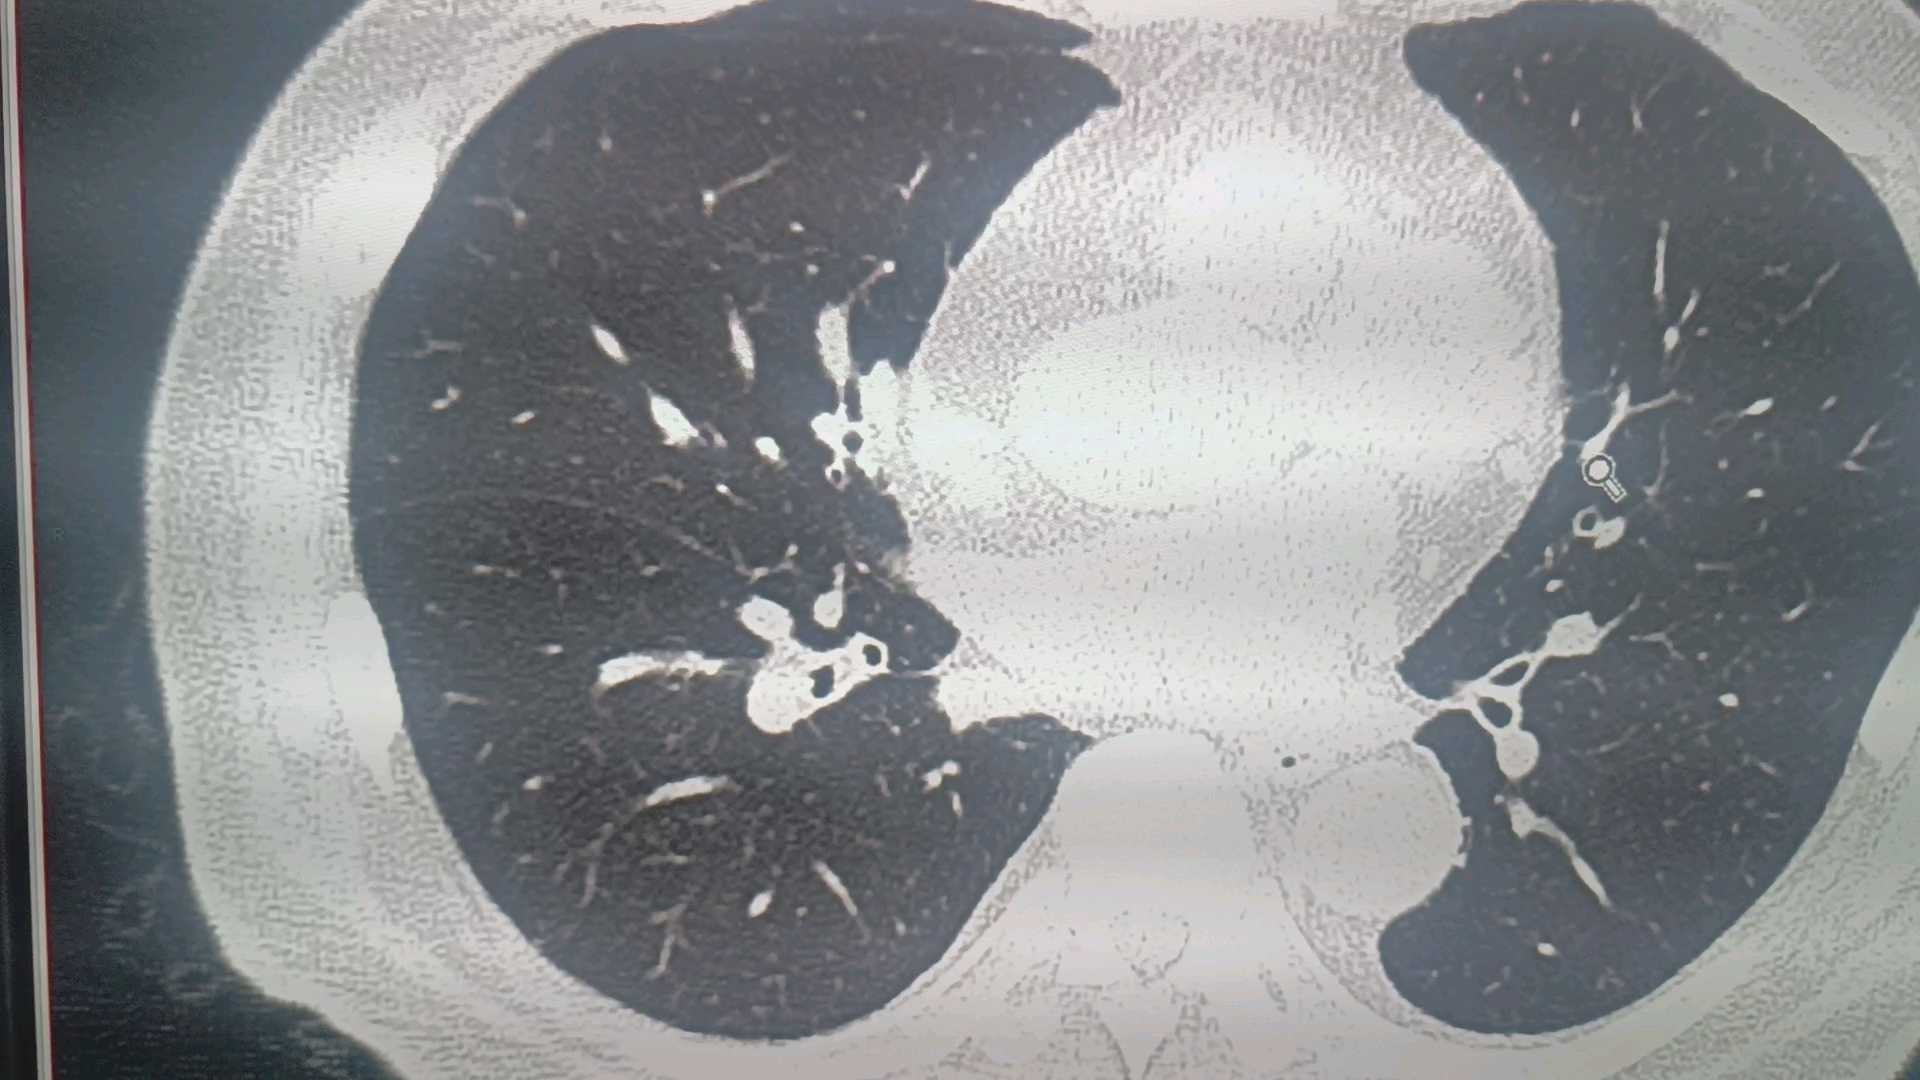

男76,发作性胸闷13年,再发5小时,初诊看不到或当成粘液栓很正常

病灶在这里:

又过了一个月,患者因胸闷再次发作就医,CT如下(距基线扫描2月),此次右肺下叶病变明显,建议做增强排除占位: